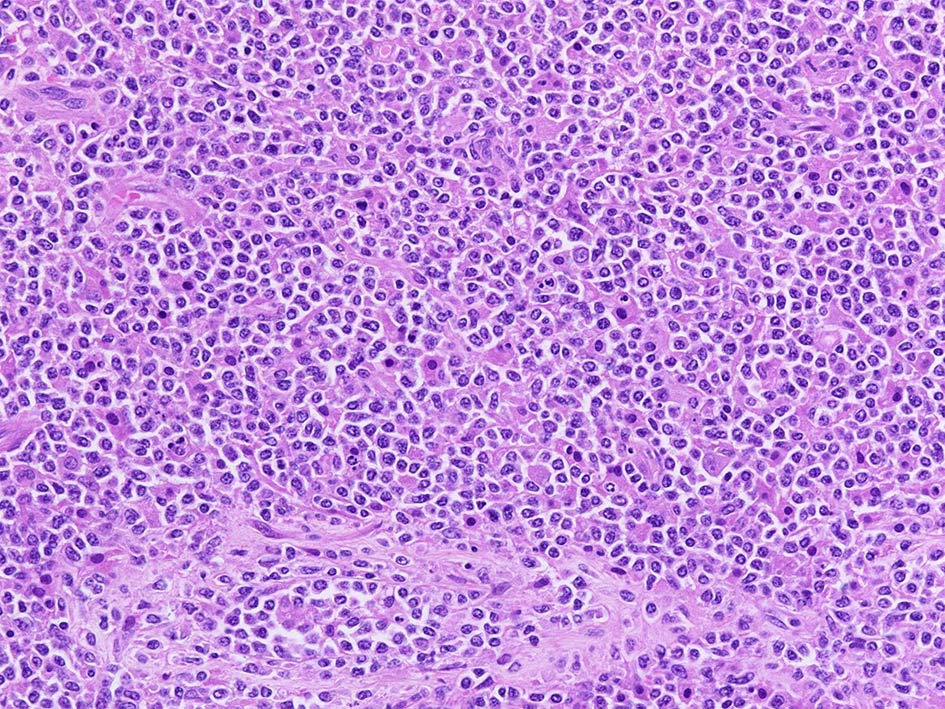

腫瘍内に壊死が認められる. 異型リンパ球の密な増殖により精細管は消失している.

腫瘍細胞はcentroblastic cells. mitosisやapoptosisが多い.